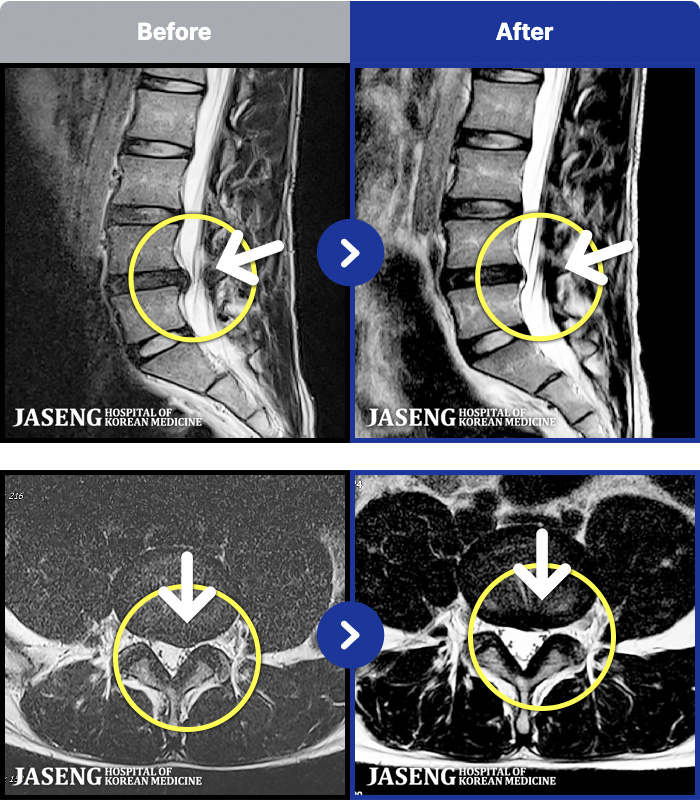

- MRI ġ

MRI ġ

MRI ũ ʸ Ȯϼ.